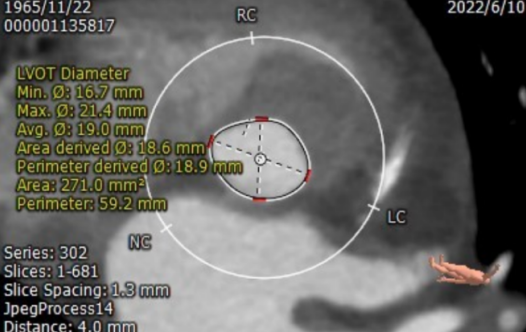

CT测量

主动脉瓣根部CT测量

瓣环周长:65.7mm;LVOT周长:59.2mm

瓣下2mm:20.4mm

瓣下4mm:19.0mm

瓣下6mm:18.8mm

瓣下8mm:19.5mm

• 患者瓣环周长65.7mm;平均直径21.2mm;LVOT周长59.2mm;平均直径19.0mm;